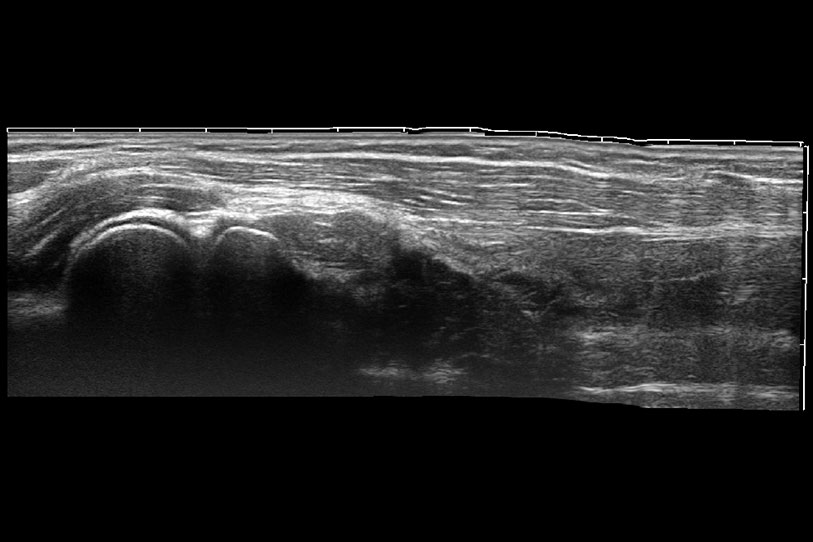

通过色彩血流和实时宽景相结合,可观察到完整的静脉或动脉的血流,方便医生检查。实时扫查过程中,如有任何操作失误也可以很容易地进行回扫擦除,而不会中断扫查。

为精细结构及组织边缘提供高清晰度的图像和更大的成像视野。帮助减轻医生的用眼疲劳,快速精准获得测量的数据。